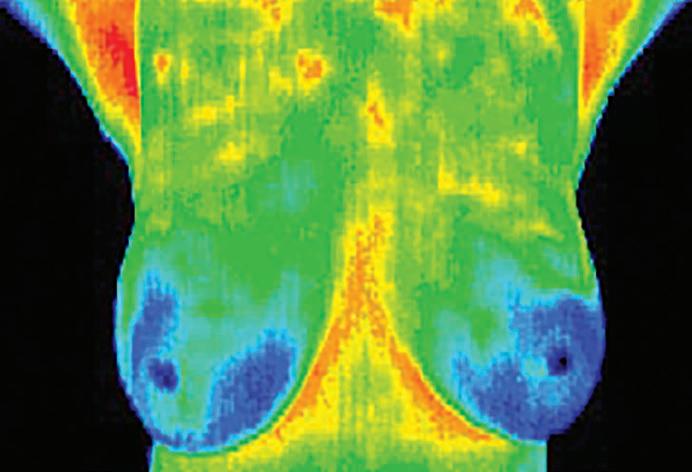

by Pamela Howard, DC, CCT

October is Breast Cancer Awareness Month, highlighting the importance of multiple strategies for early detection and risk assessment. Conventional imaging techniques, including mammography, ultrasound and magnetic resonance imaging, primarily identify structural abnormalities such as tumors. But breast thermography, by contrast, is a noninvasive imaging method that employs infrared cameras to measure skin surface temperature and detect heat patterns associated with inflammation and increased blood flow.

The medical use of breast thermography dates back to 1956, when Canadian surgeon Dr. Ray Lawson documented temperature variations associated with a large breast mass. His work initiated decades of research into thermography’s potential role as an adjunctive screening method.

The advantage of thermography is that it detects physiological changes—specifically the vascular and metabolic activity that can precede tumor formation. By tracking variations in blood vessel activity over time, thermography may indicate areas of concern suggestive of a precancerous state.

The procedure is conducted in a temperature-controlled environment. Patients disrobe from the waist up and allow the breasts to acclimate to room temperature before imaging. Next, they stand or sit in front of a special infrared camera while a technician takes images of the skin’s surface temperature. Areas of increased heat are revealed, appearing as red “hot spots,” contrasted against cooler tissue in blue, green or yellow.

An initial thermography scan creates a “thermal thumbprint” used as a baseline for comparison. Two scans, usually taken three months apart, are required to confirm stable patterns of heat and vascular activity, since thermography measures function rather than producing a static image. After this baseline is established, annual studies are recommended to track changes over time.

The U.S. Food and Drug Administration has cleared thermography for use only in combination with other screening or diagnostic procedures such as mammography. Unlike mammography, it does not expose patients to radiation and does not require compression of breast tissue. It is not approved as a standalone method for the detection, diagnosis or screening of breast cancer. As research continues, thermography remains a supplemental option within a broader strategy of preventive breast health.

Dr. Pamela Howard is a doctor of chiropractic and a certified clinical thermographer. She is the owner of Advanced Thermal Imaging, located at 550 Coventry Dr., in Mechanicsburg. For more information or to schedule an appointment, call 866-522-3484 or visit AThermalImage.com. See listing, page 34.